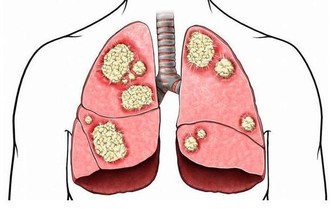

藥書泰斗嘉眾草師表示,根據統計發現,國人尿酸過高的情形日趨嚴重,而尿酸過高的患者極有會發展成痛風。

高尿酸的形成主要原因有二:

(1)尿酸產生過多;

(2)尿酸排泄減少。

許多患者只有血清尿酸鹽濃度的增高而沒有臨床症狀,只有在發生關節炎時才稱為痛風。痛風的病理基礎是高尿酸血症,正常人血尿酸值是男性2.4-7mg/dL,女性1.6-5.2mg/dL。

當體液中尿酸濃度超過此值時,將因過剩而在組織中沉積,這種尿酸鹽的結晶沉積在關節滑膜、關節骨、軟骨而導致痛風性關節炎,沉積在皮下則形成痛風石。中西醫均會要求痛風患者不可以攝取高普林食物,然而這些食物可以說是最起碼的美食,要痛風病患完全不吃這些食物,說真的,這種治療的犧牲代價還不小呢!